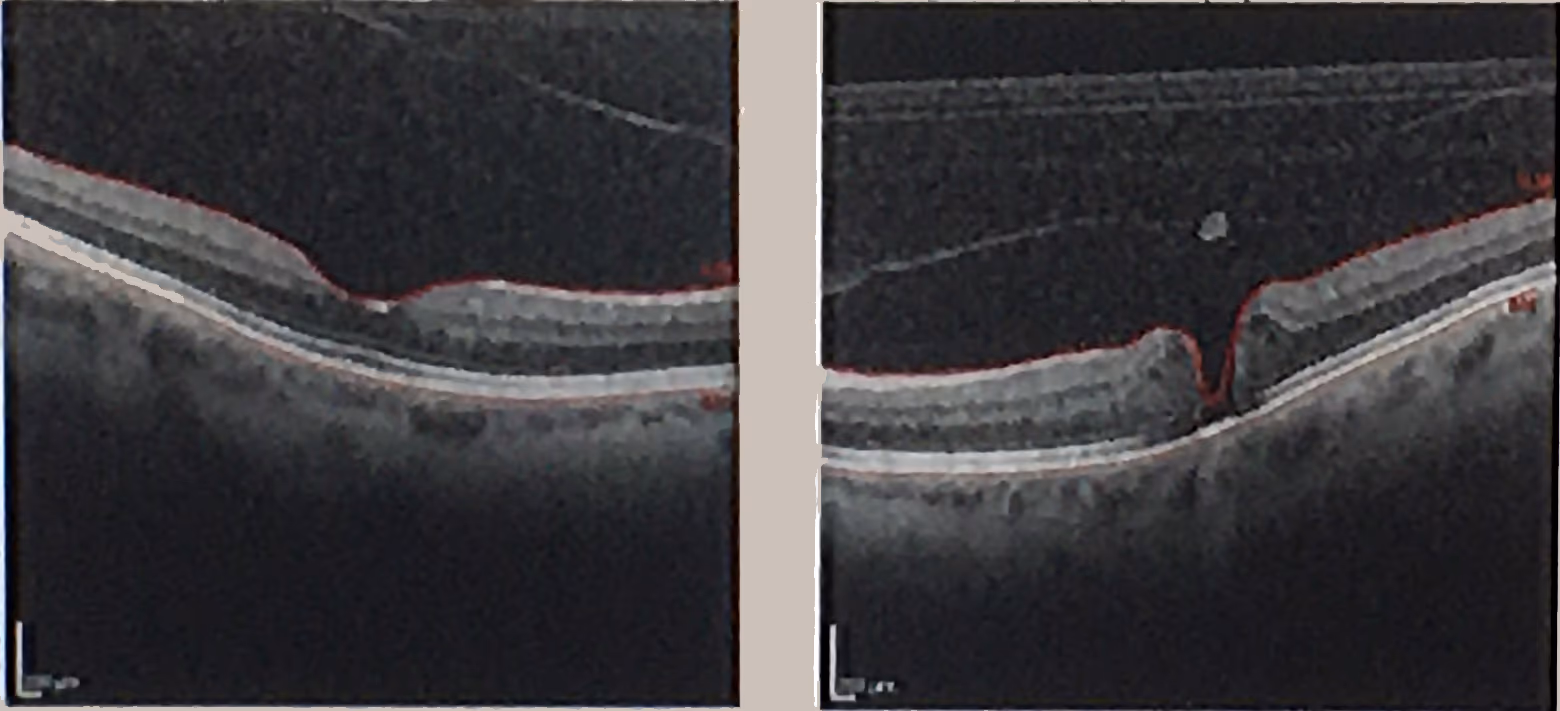

Cada tratamento deve ser indicado após avaliação detalhada da córnea, do cristalino, da retina, do nervo óptico e do histórico do paciente.